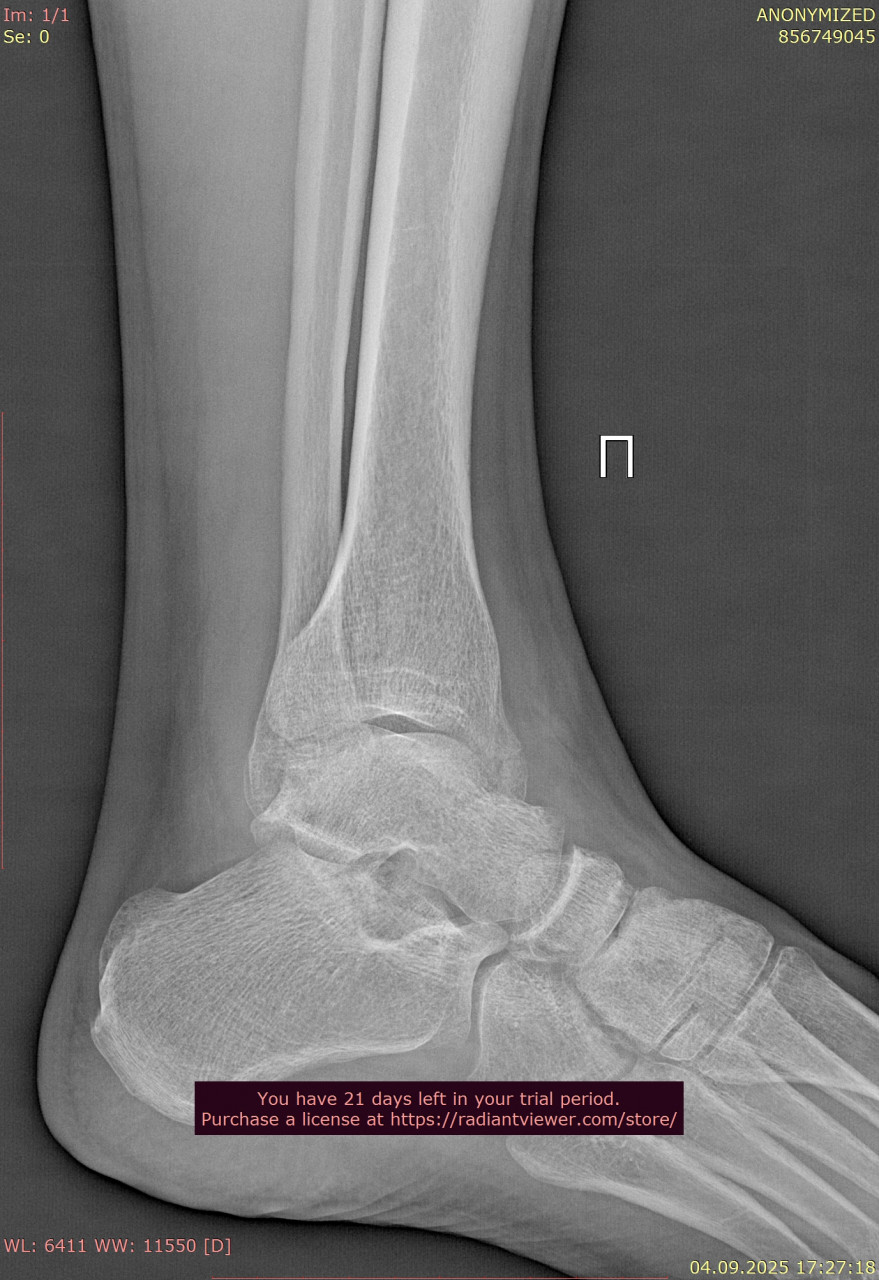

Посмотрите, пожалуйста, снимки голеностопного сустава от 23.06.2025, когда был перелом, и спустя почти 11 недель от 04.09.2025. Переломы срослись нормально? нужно ли делать еще один рентген в будущем? От 23.06.2025 прикрепляю только одну проекцию из за лимита сайта.

Здравствуйте. По вашим снимкам костная мозоль сформировалась, перелом срастается удовлетворительно, признаков смещения нет. Дополнительный рентген обычно не требуется, если нет боли или отёка, но окончательное решение принимает лечащий травматолог при очном осмотре.